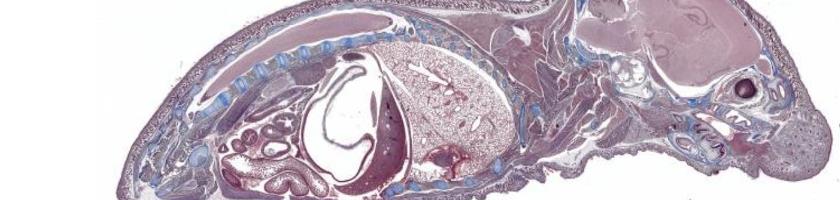

These are samples of the various microscopes we have in stock